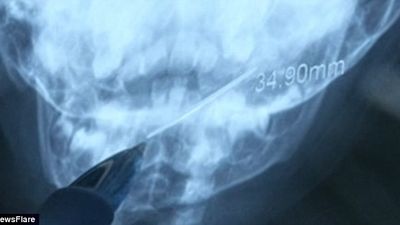

Pas fotografimit me rreze X, është zbuluar gjilpëra që ndodhej në fytin e fëmijës, me ç’rast i është nënshtruar intervenimit të menjëhershëm.